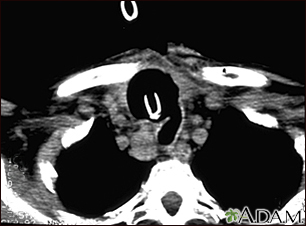

Thyroid cancer - CT scanBackThyroid cancer - CT scanThis CT scan of the upper chest (thorax) shows a malignant thyroid tumor (cancer). The dark area around the trachea (marked by the white U-shaped tip of the respiratory tube) is an area where normal tissue has been eroded and died (necrosis) as a result of tumor growth. E-mail FormEmail ResultsName:Email address:Recipients Name:Recipients address:Message: